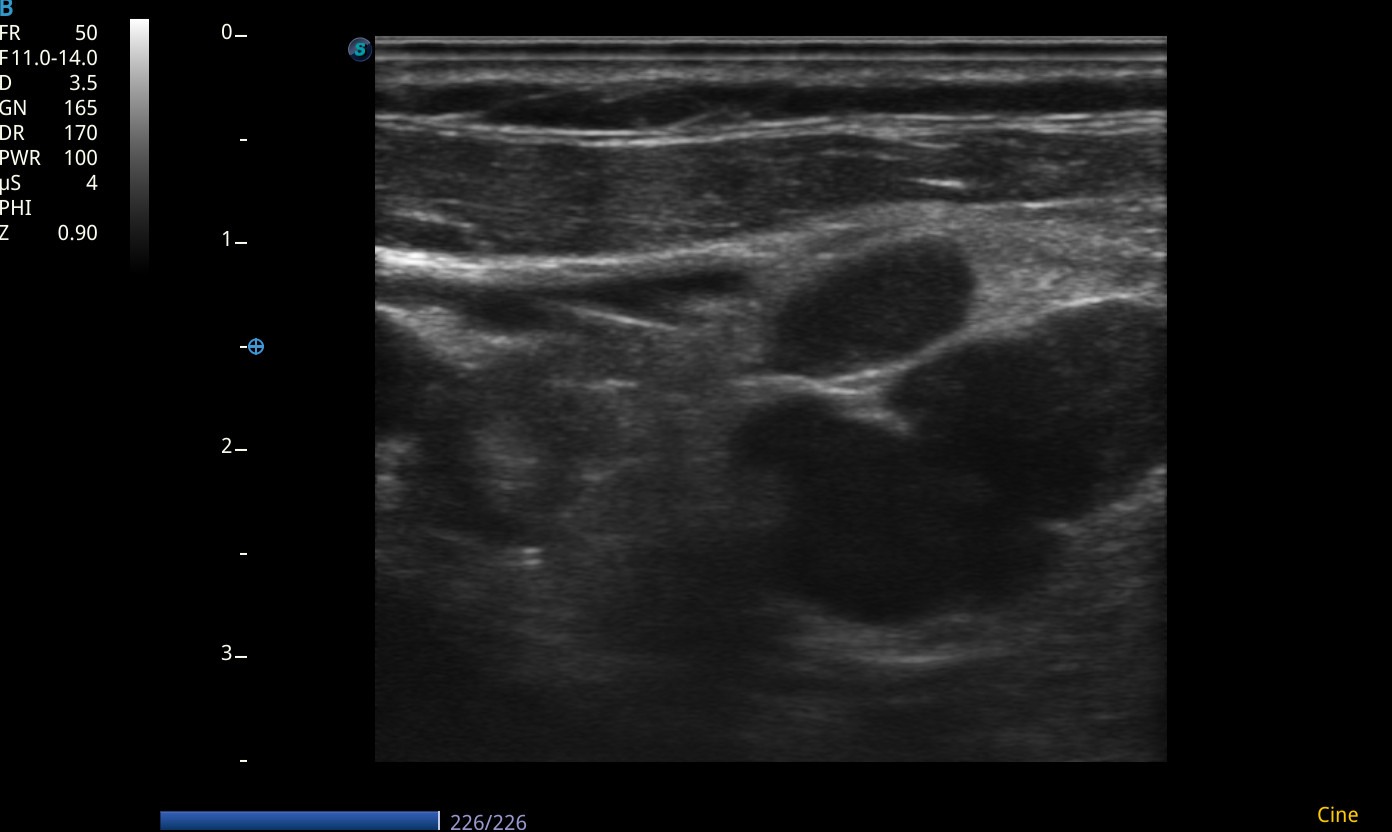

En las imágenes ecográficas del centro de salud se visualizan los siguientes hallazgos:

Conglomerado adenopático en cadena ganglionar laterocervical izquierda. Los ganglios visualizados presentan márgenes poco definidos/irregulares, ausencia de hilio ecogénico, ecogenicidad heterogénea, y algunos con forma redondeada, características con alta sospecha de malignidad. Dadas tales características y antecedentes personales, se deriva de forma preferente a Medicina Interna, para completar estudio de adenopatías.